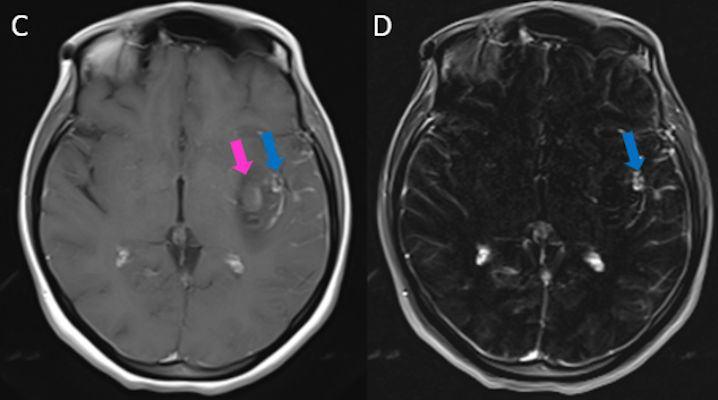

- Kontrastlı T1A görüntüde (C) ve kontrastlı T1A çıkarma görüntüde (D) medialde bulunan alanda kontrastlanma izlenmezken (ok), lateralde bulunan boyutça daha küçük alanda kontrastlanma izleniyor (ok). Ayrıca anevrizma komşuğunda silvian fissürde leptomeningeal kontrastlanma görülüyor.